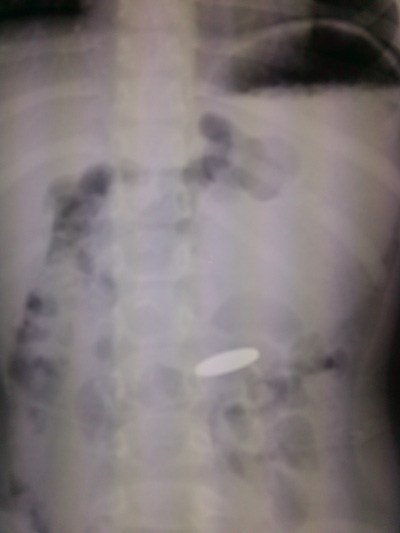

Bác sĩ cho chụp X-quang kiểm tra và xác định đồng xu nằm trong dạ dày.

Đồng xu nằm trong dạ dày bé V., nhìn thấy qua X-quang - Ảnh: Bệnh viện cung cấp